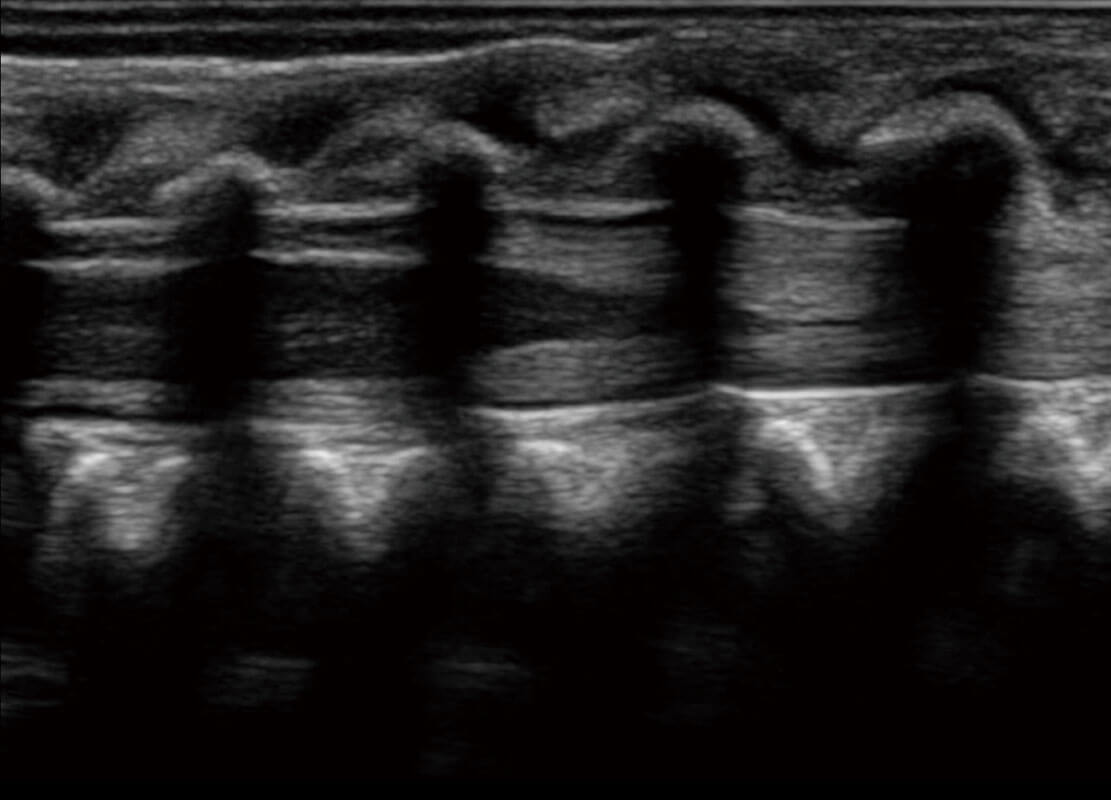

P60搭载宽频带线阵探头、宽景成像、弹性成像技术,为您提供乳腺应用方案。P60支持高频相控阵探头、线阵探头、腹部高频探头、腹部微凸探头等,丰富的探头群搭载敏感的彩色血流成像,适用于新生儿多种脏器检测要求,满足新生儿筛查需求。

新生儿心脏